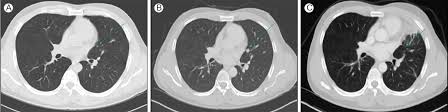

- 흉부 X‑선 또는 흉부 CT로 발견

- 결절 크기·형태·경계·석회화 여부 등 특징 분석